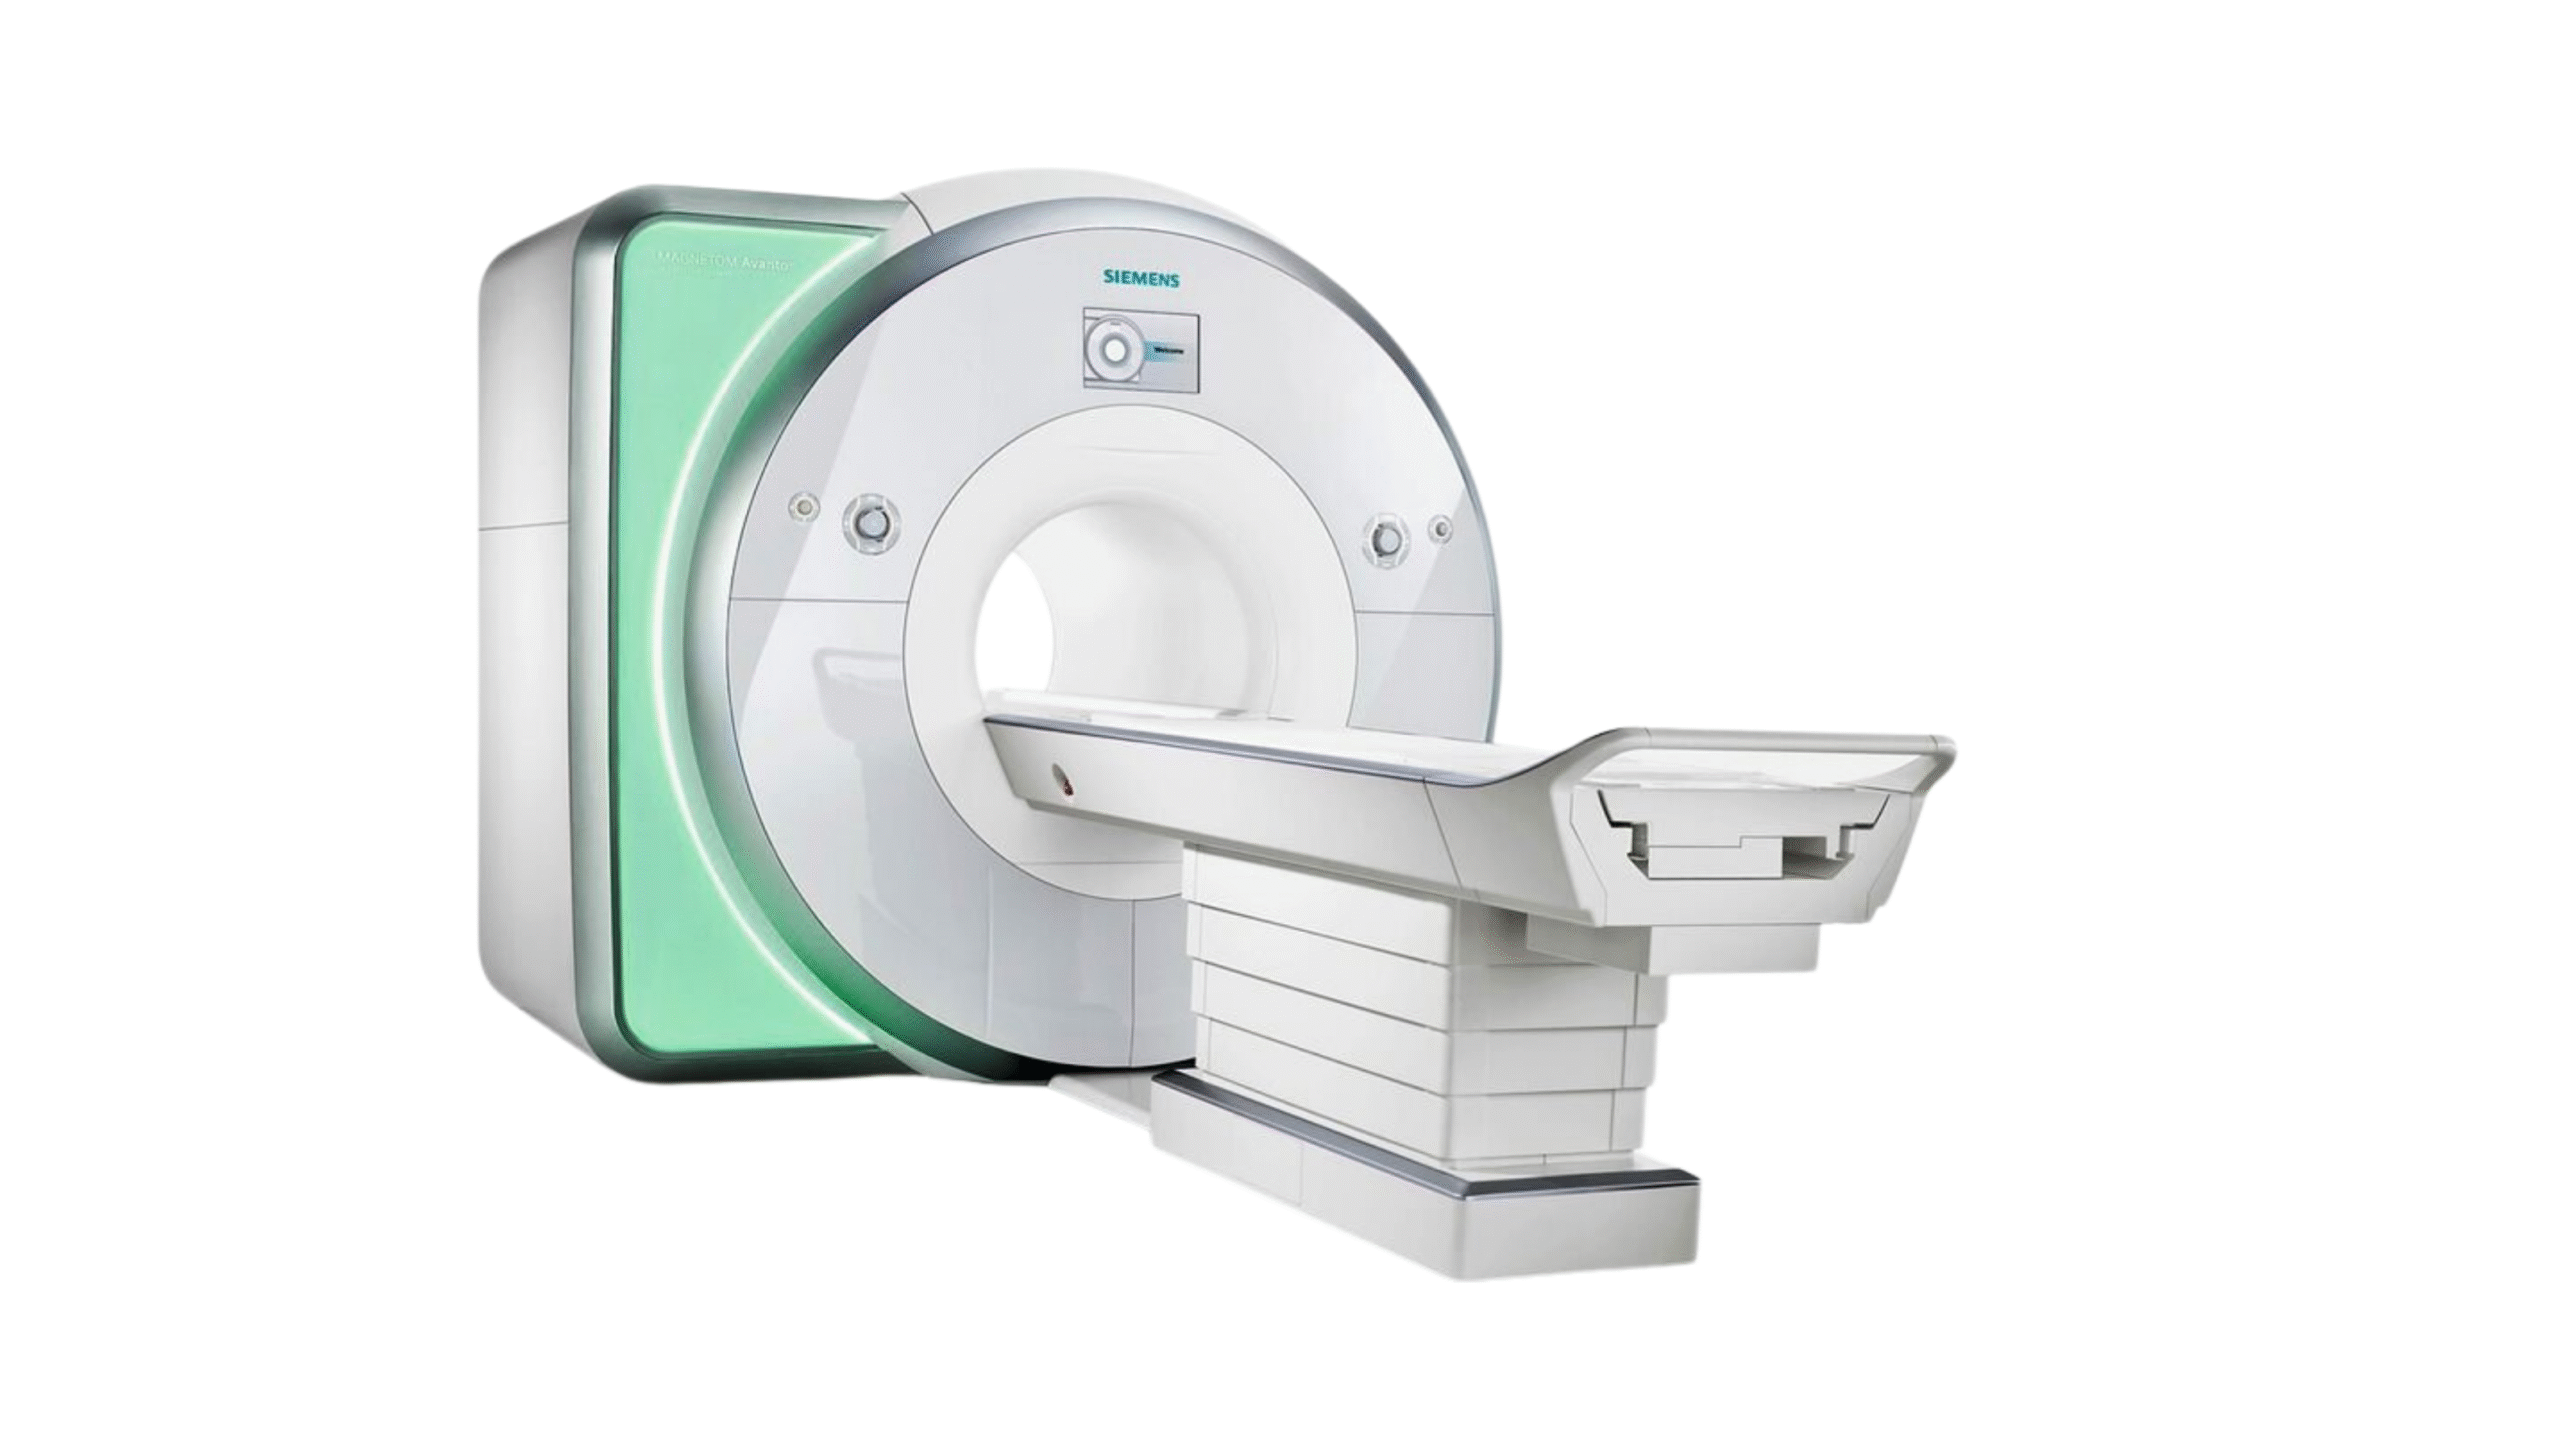

Products